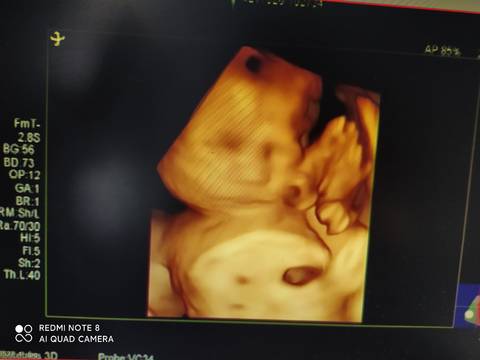

悬浮肚,太累人了,不知男孩女孩,医生只说宝宝大长腿

journal_insert_pic_1683086814journal_insert_pic_1683086854journal_insert_pic_1683086904